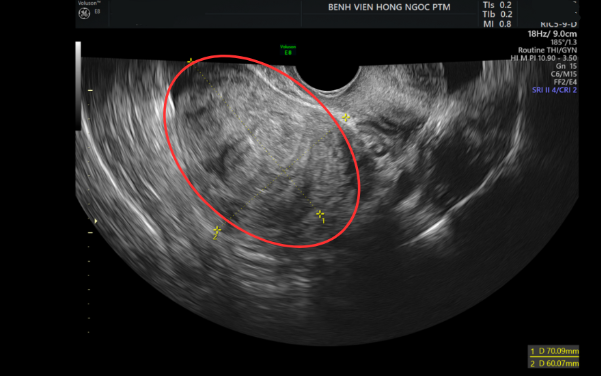

Thế nhưng, suốt 5 năm miệt mài chạy chữa, bệnh vẫn không thuyên giảm. Gần đây, chị thường xuyên cảm nhận rõ khối u nổi ở vùng bụng dưới, kèm cảm giác chướng bụng và đau âm ỉ. Kết quả siêu âm cho thấy khối u đã đạt kích thước hơn 7cm, chiếm gần nửa tử cung, song chị vẫn chần chừ chưa phẫu thuật vì lo ngại "dao kéo" ảnh hưởng đến sức khỏe.

Hình ảnh siêu âm khối u xơ kích thước hơn 7cm làm biến dạng tử cung.

Sau khi tìm hiểu và được tư vấn, chị Vân quyết định tìm đến BVĐK Hồng Ngọc Phúc Trường Minh. Tại đây, sau khi khám và siêu âm, các bác sĩ xác định khối u xơ tử cung kích thước 60x70mm ở vị trí FIGO L6, cùng khối u nhỏ khoảng 15mm ở mặt sau gây biến dạng tử cung. "Với kích thước và vị trí của khối u, phương án phẫu thuật nội soi bóc nhân xơ sẽ là lựa chọn tối ưu. Đây là phương án điều trị xâm lấn tối thiểu giúp loại bỏ khối u một cách triệt để cũng như đảm bảo sức khỏe và khả năng hồi phục nhanh chóng cho người bệnh", ThS.BSCKII Nguyễn Văn Xuyên (Trưởng Đơn nguyên Phụ khoa và Tuyến vú - Khoa Sản Phụ khoa - BVĐK Hồng Ngọc Phúc Trường Minh) phân tích.